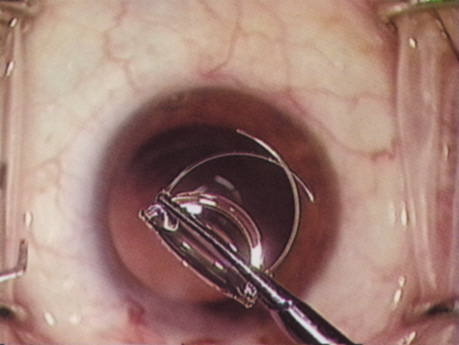

HYDRODISSECTION

Hydrodissection can be performed after the surgeon has successfully completed capsulorrhexis.97 If the capsulorrhexis is not intact, fluid forced around the interior of the capsule may cause the bag to splay open. With capsulorrhexis, hydrodissection is a safe and extremely useful maneuver. Hydrodissection can be thought of as two maneuvers: hydrodelineation and cortical cleaving hydrodissection. By placing a 27-gauge cannula on a syringe filled with balanced saline solution (BSS), the surgeon can direct fluid beneath the residual anterior capsular rim to create a cleavage plane. Depending on the direction the fluid wave takes, different lamellae of the cataract will be separated. Hydrodelineation is the term used when the cleavage plane separates the adult nucleus from the fetal nucleus or the adult nucleus from the more peripheral epinucleus. Hydrodelineation often results in the characteristic golden ring sign (Fig. 11). Cortical cleavage occurs when the cortex is separated from the capsular bag (Fig. 12). Finding the cortical cleavage plane may be facilitated by gently lifting the capsular margin away from the cortex with the BSS cannula before injecting. Several small bursts of fluid allow the surgeon to monitor progress of the fluid wave. When dealing with a soft nucleus, the authors strive to perform true cortical cleaving hydrodissection. For a hard nucleus, hydrodelineation allows manipulation of less of the nuclear bulk, although the remaining epinuclear shell must be addressed in an additional step. Hydrodelineation is particularly useful if the nucleus is not freely mobile after cortical cleaving hydrodissection.

Fig. 11. A crisp “golden ring” is seen from the fluid cleft between the epinucleus and nucleus with hydrodelineation.

Fig. 12. Hydrodissection, performed subincisionally with a 27-gauge J-cannula, produces a cleavage plane between the capsule and the cortex. The small blue arrows indicate the advancing fluid wave.